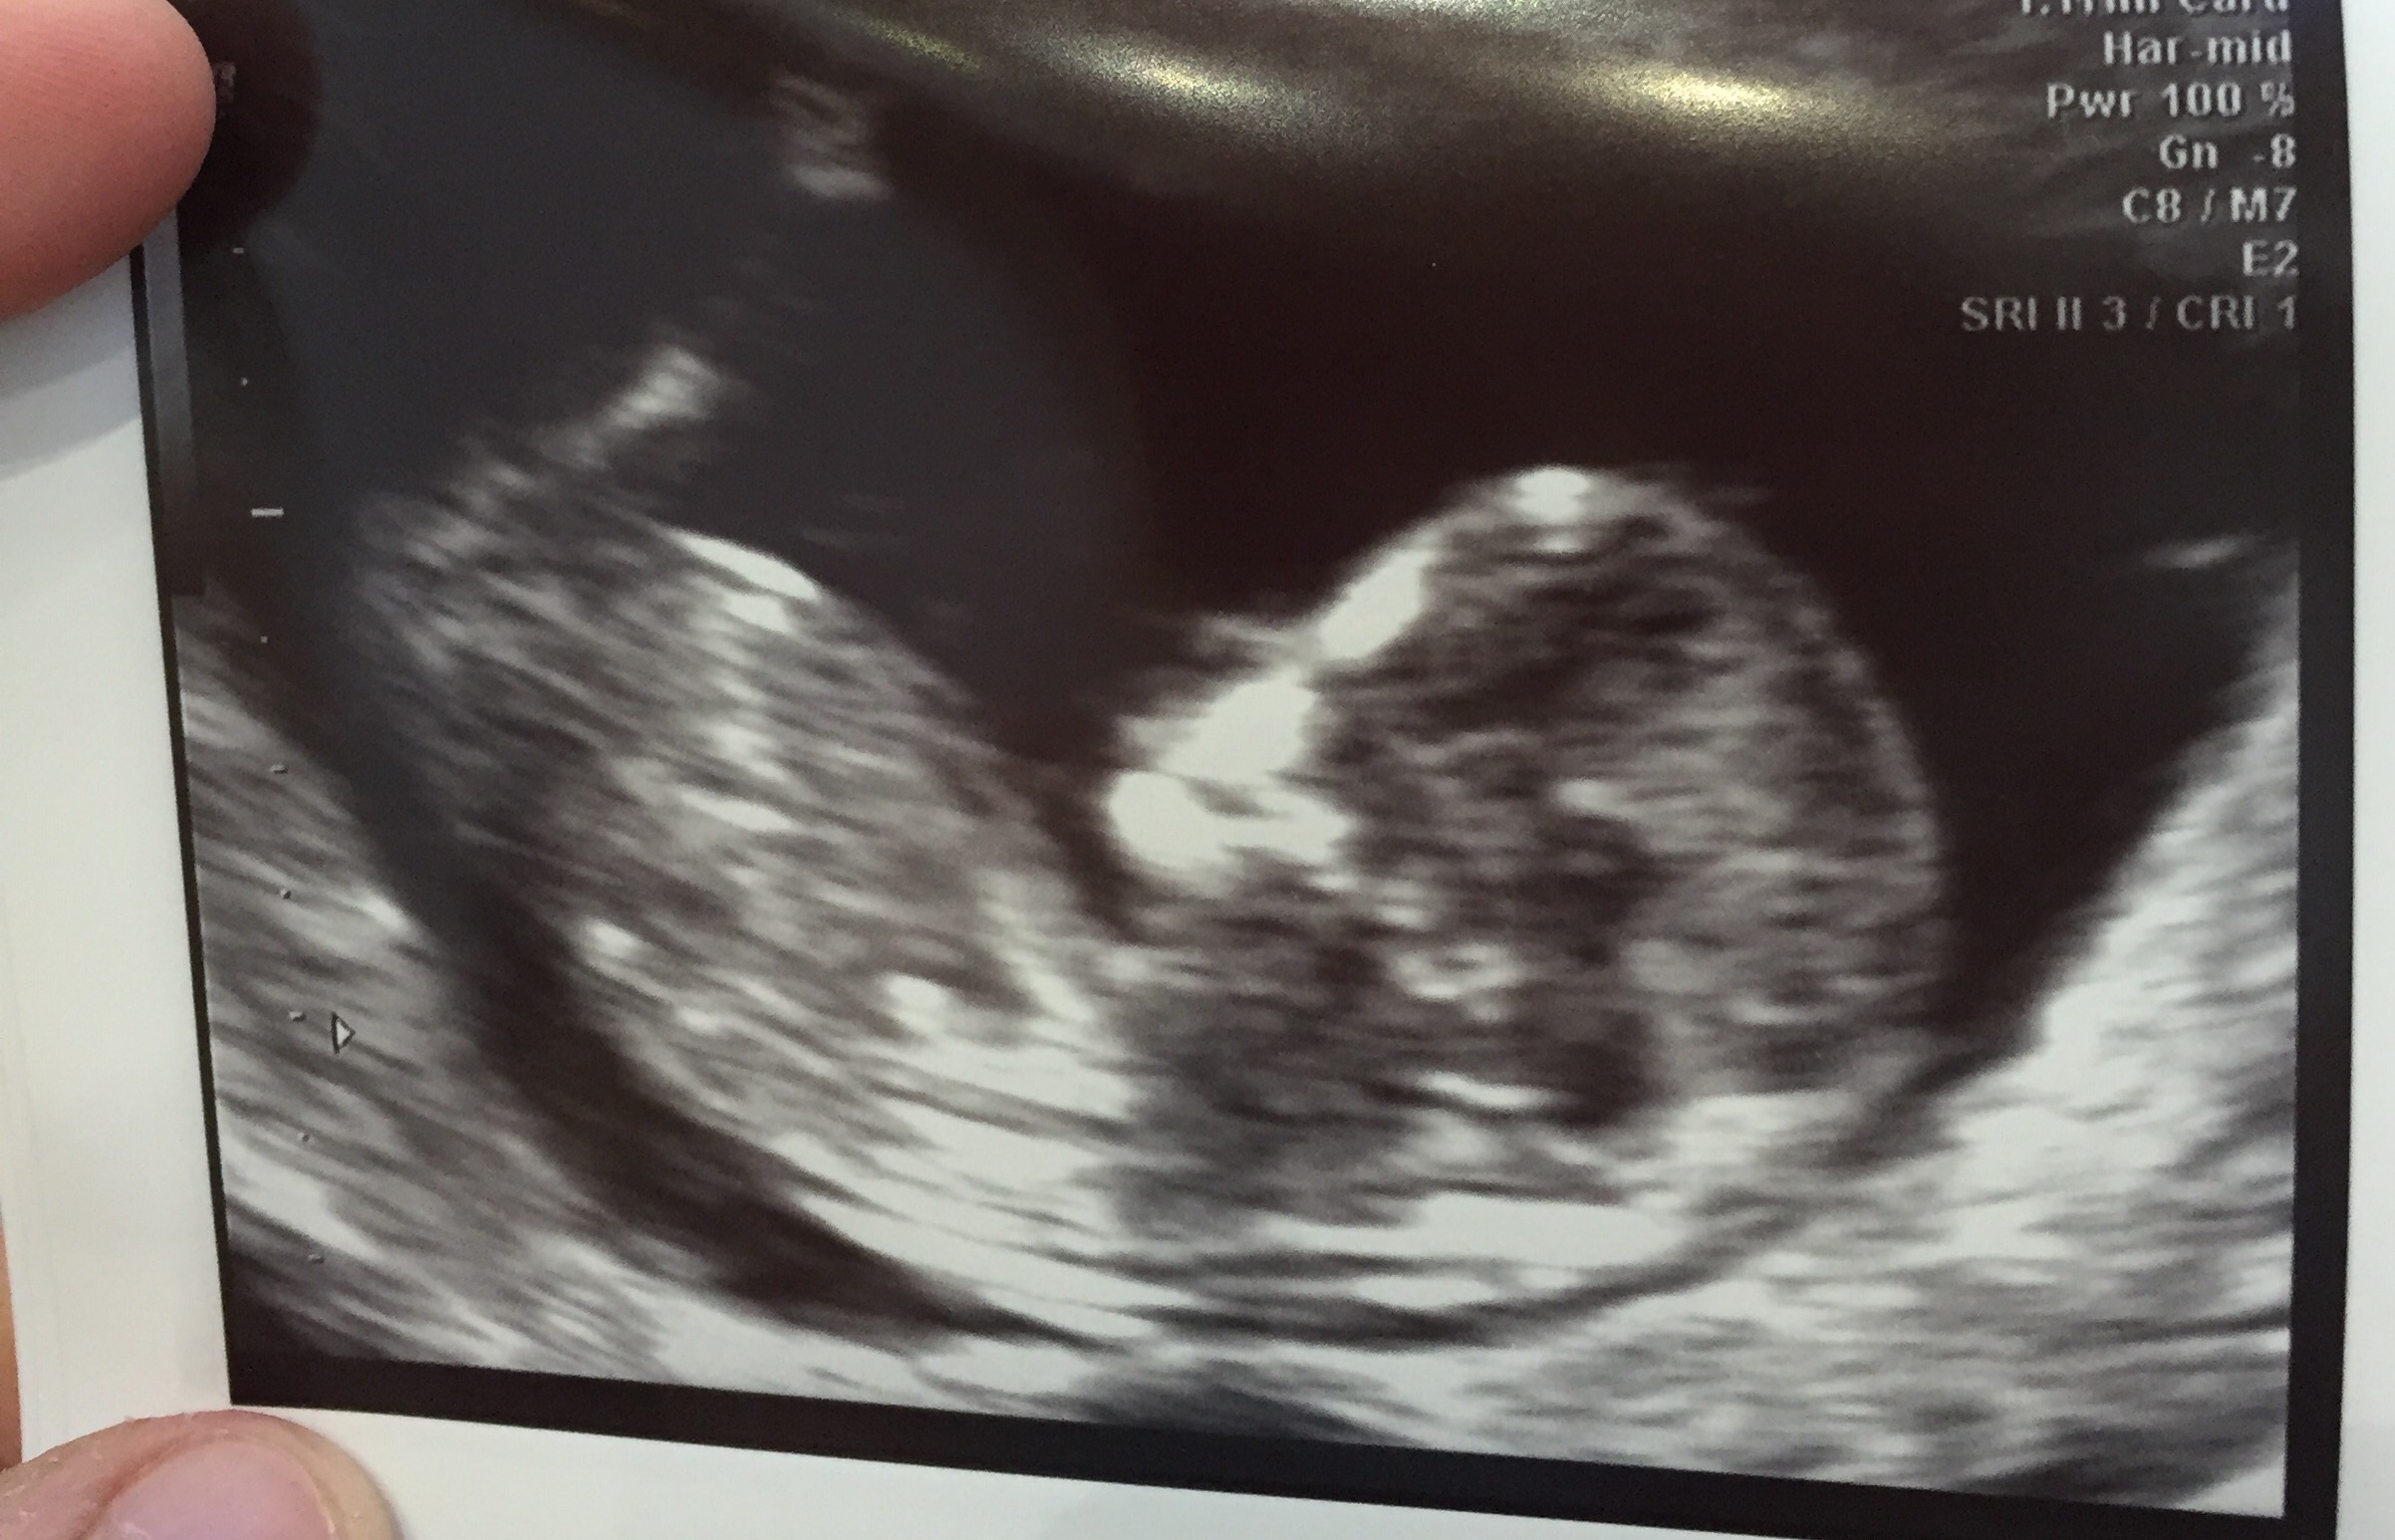

hey beautiful ladies how many of you have had your first ultrasound? How was your experience? I couldnt hold my tears when i saw the tiny being inside me with its heart beating. Such a wonderful thing to experience really:) my husband just couldnt hold smiling and looking away from the baby. Absolutely loved the experience. Here is the pic of the first ultrasound. The baby is 8 weeks 5 days as of today. Please share your experience. Would love to know